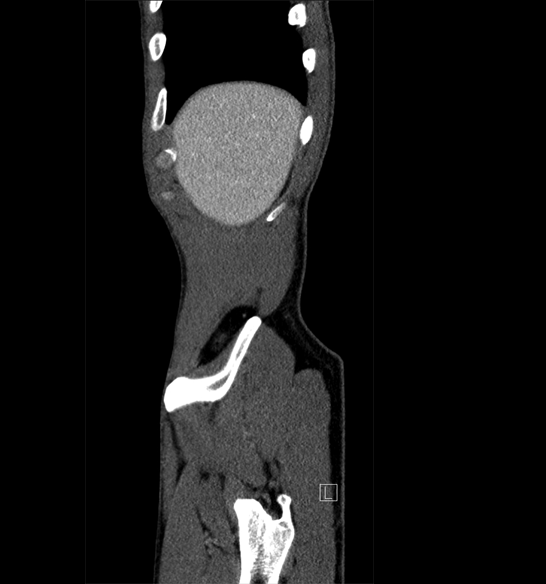

Body

Covers abdominal CT anatomy.